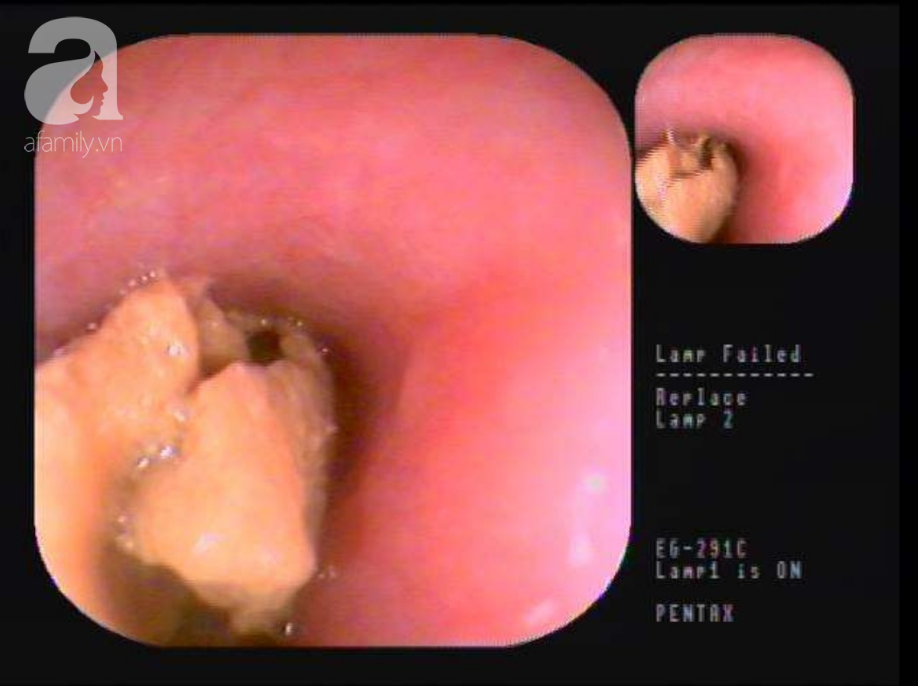

Bác sĩ Lê Xuân Đức, Trưởng khoa Nội Tổng quát một BV ở Bình Dương cho biết, vừa qua nơi đây đã thực hiện thành công thủ thuật nội soi gắp dị vật là một phần thức ăn lớn (thịt heo) đường kính khoảng 5cm đã bị vữa trong thực quản rất nguy hiểm cho một người đàn ông.

Bác sĩ Đức chia sẻ: "Đây là một trường hợp đặc biệt bởi phần dị vật là khối thức ăn khá lớn đã bị vỡ nát. Để lấy dị vật ra, ekip bác sĩ phải chia dị vật ra thành nhiều phần nhỏ. Sau hơn 45 phút, các bác sĩ đã gắp hoàn toàn phần thức ăn ra khỏi thực quản cho người bệnh".